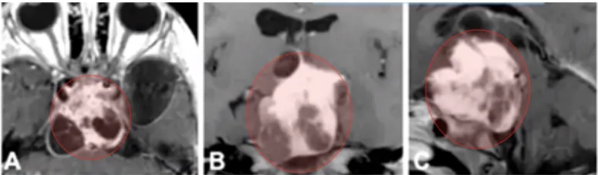

所谓的视力模糊,实则是这一巨大肿瘤对患儿双眼视神经压迫所...

医生表示,手术中发现实为视神经胶质瘤,若予以切除,孩子将...